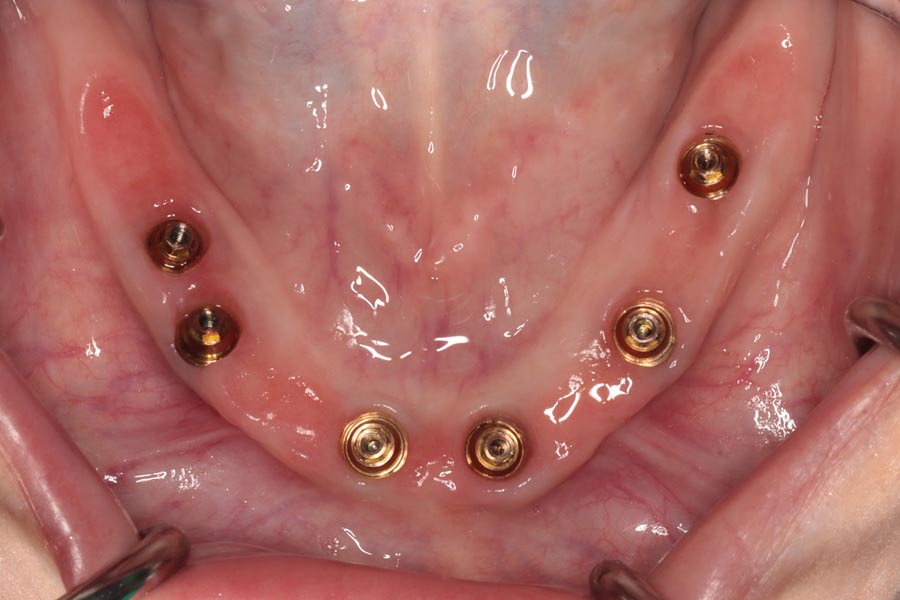

On the day of delivery, tissues are pink and healthy. The provisionals have helped to shape them perfectly to prepare them for the definitive restorations.

The definitive bridges are delivered, the bite is verified, and the screws are torqued down firmly. The final result is strong, functional, and esthetic restorations that will serve the patient well for years to come.